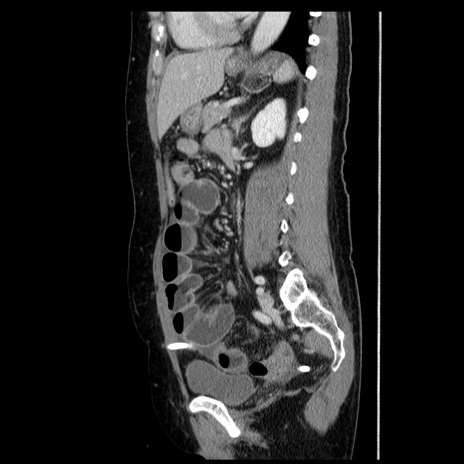

症例6(矢状断像)

【症例】50歳代女性

【主訴】下腹部痛

【現病歴】本日朝より下痢2回あり。 昼食を食べた後、嘔吐3回、下腹部痛認め、症状軽快せず、当院救急搬送。

最終食事:本日昼(生ものなし)。 昨日の夜、刺身を食ぺたとのこと。周囲に同様の症状の者なし。普段、排便は毎日あるとのこと。

【既往歴】卵巣癌術後(8年前に当院で卵巣摘出)

【身体所見】 意識清明、腹部:平坦、腸蠕動音→、やや硬、下腹部自発痛・圧痛あり、反跳痛あり、筋性防御なし。

【データ】WBC 16000、CRP 0.01